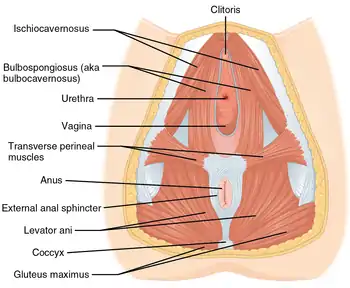

Muscles of the female perineum. (Urogenital triangle is roughly equal to top half of diagram.) | |

The urogenital triangle is the anterior part of the perineum. In female mammals, it contains the vagina and associated parts of the internal genitalia.

The urogenital triangle is the area bound by a triangle with one vertex at the pubic symphysis and the two other vertices at the iliac tuberosities of the pelvic bone.

Components

As might be expected, the contents of the urogenital triangle differ greatly between the male and the female. Some of the components include:[1]

- Posterior scrotal nerves / posterior labial nerves

- Urethra

- Vagina

- Bulbourethral gland / Bartholin's gland

- Muscles

- Crus penis / clitoral crura

- Bulb of penis / vestibular bulb

- Urogenital diaphragm

- Muscular perineal body

- Superficial and deep perineal pouch

- Blood vessels and lymphatics